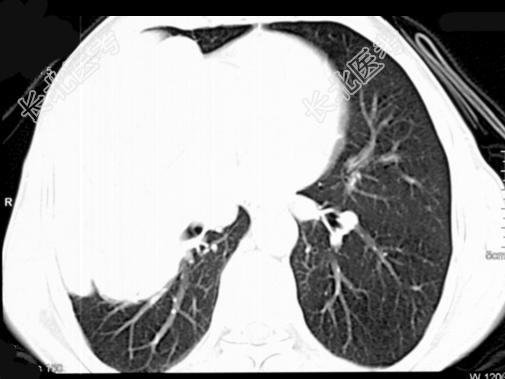

- 单项选择题50岁,男, 右侧胸痛、咳嗽、咯血3月,结合图像, 最可能的诊断是 ( )